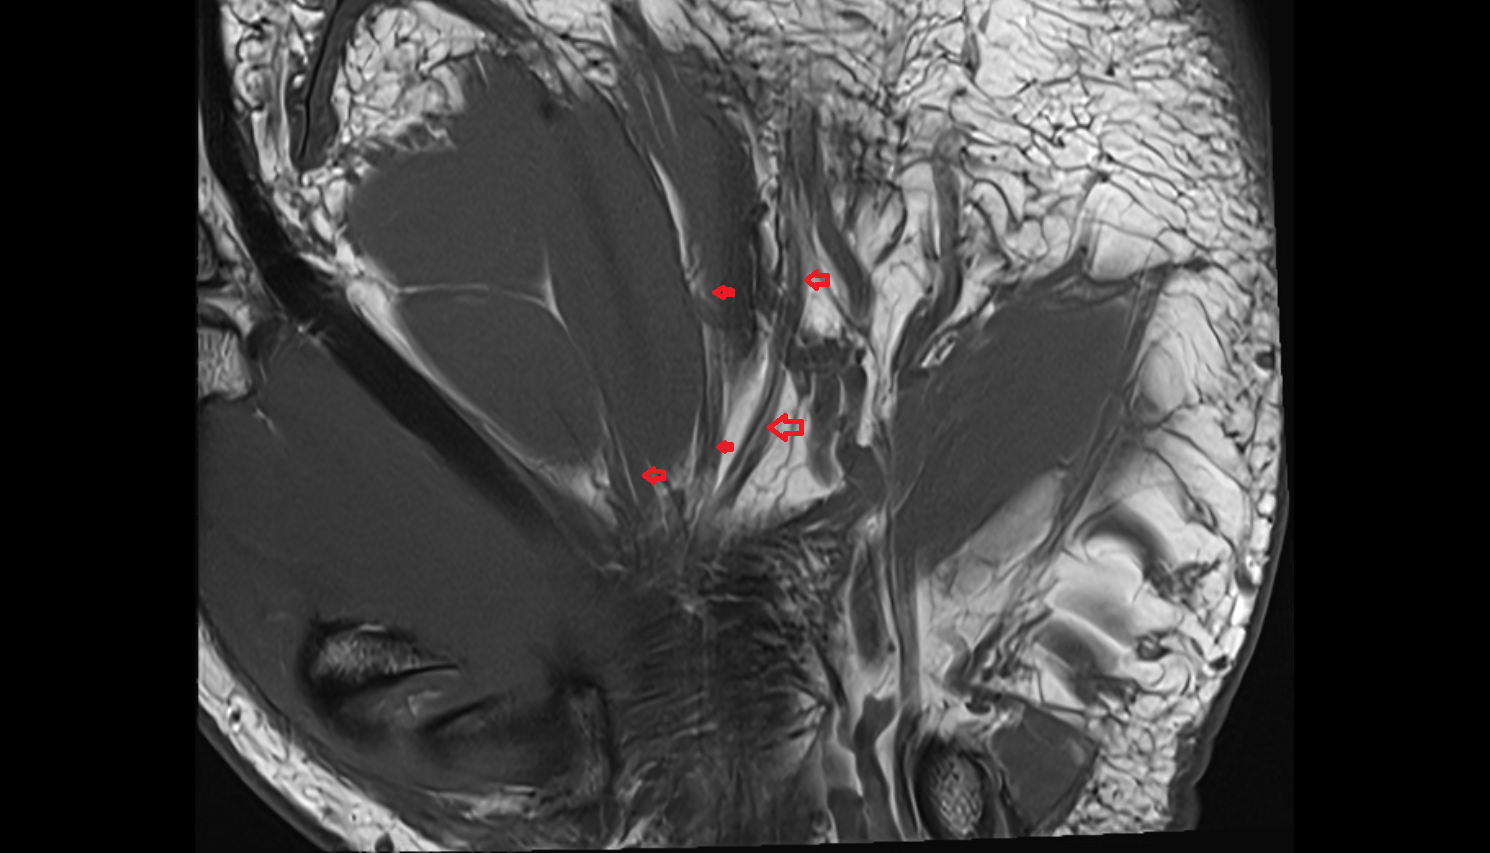

- Temporomandibular joint

- Articular disc of temporomandibular joint

- Articular eminence

- Mandibular condyle

- Mandibular fossa

- Superior head of lateral pterygoid muscle

- Inferior head of lateral pterygoid muscle

- Lateral pterygoid muscle